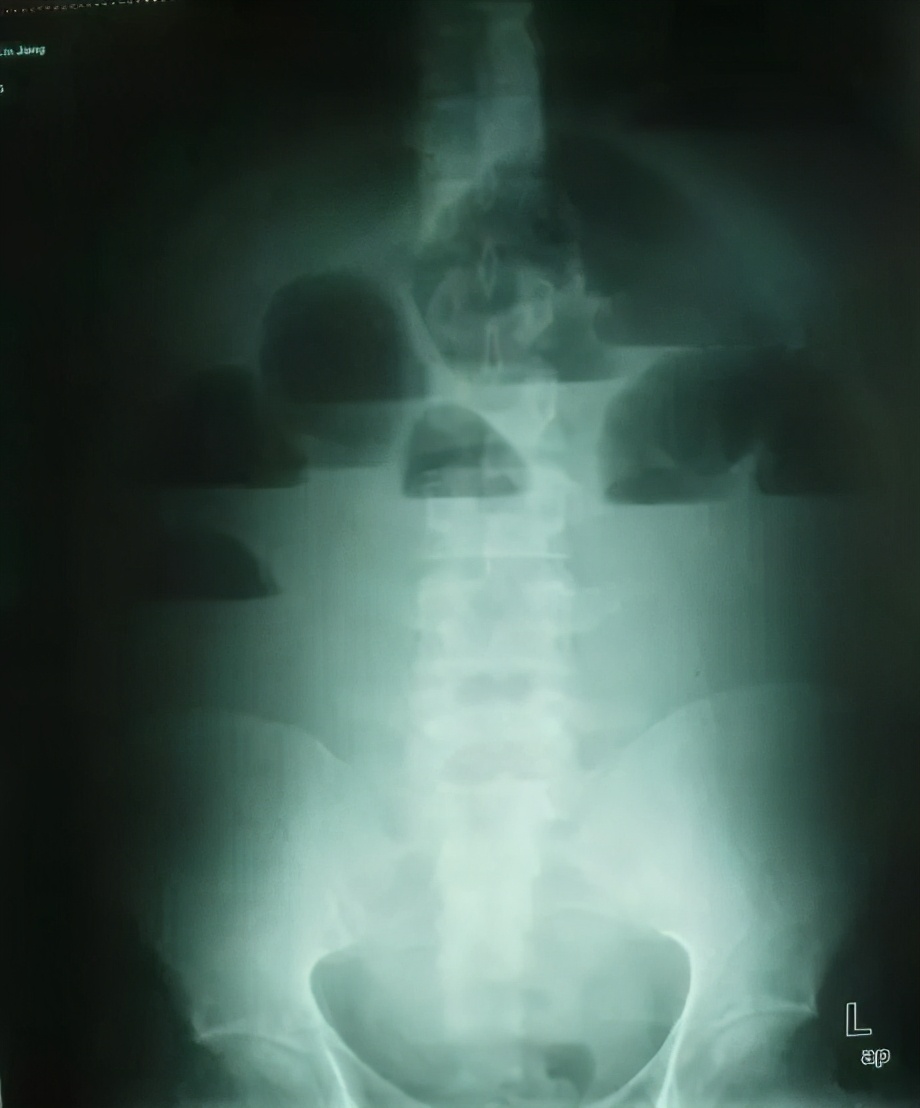

(1)立位或卧位腹平片: 肠梗阻4-6小时后即可检出肠袢胀气,表现为多个阶梯状气液平面;空肠粘膜的环状皱壁呈“鱼骨刺”样;绞窄性肠梗阻可见孤立、突出、胀大肠袢。 注意:X线阴性不能排除肠梗阻。怀疑肠套叠,肠扭转或结直肠癌时作钡灌肠。

阶梯状液气平面